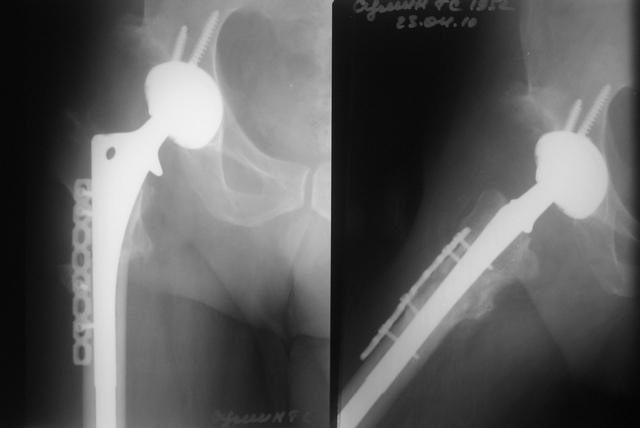

Выполнена одномоментная коррекция деформации, эндопротезирование DePyu Pinnacle-AML.Пластинка с деротационной целью. При использовании ножки с прямоугольным сечением, думаю можно и без нее